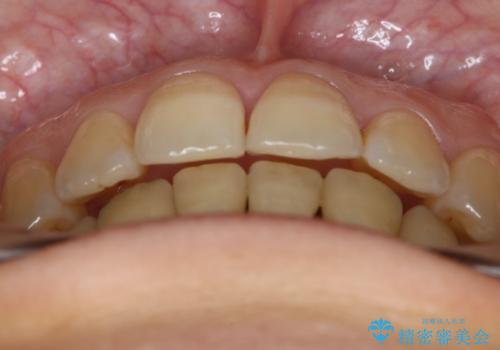

抜歯を行うことで前歯を後ろへ下げるスペースを獲得し、口元の突出感や歯のガタつきを改善していきました。

- 前歯を後ろへ下げることを主訴に来院された患者様です。

口元の突出感の改善や歯の移動量などを考慮し、抜歯を伴うワイヤー矯正での治療を選択しました。